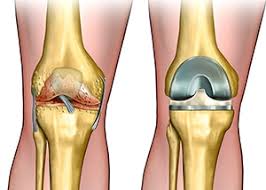

무릎 인공관절 수술, 왜 필요한가요?

무릎관절은 체중을 가장 많이 지탱하는 관절입니다. 나이가 들수록 연골은 점차 마모되고, 충격을 흡수하는 능력도 감소합니다. 이로 인해 통증, 뻣뻣함, 운동 제한이 생기며, 이런 증상이 악화되면 인공관절 수술이 필요해집니다.

퇴행성 관절염 외에도 류마티스 관절염이나 외상 후 관절 손상이 심각할 경우 수술이 권유되며, 수술을 통해 환자는 통증 없이 보행이 가능해지고 일상생활로 복귀할 수 있게 됩니다.